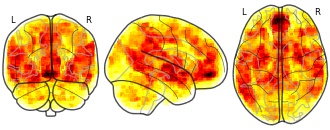

The neural basis of effort valuation: A meta-analysis of functional magnetic...

EmailClick to copy linkLink copied Cite(2020). The neural basis of effort valuation: A meta-analysis of functional magnetic resonance imaging studies: Net Value [Dataset]. http://identifiers.org/neurovault.image:440381niftiAvailable download formatsUnique identifierhttps://identifiers.org/neurovault.image:440381Dataset updatedDec 28, 2020License

Cite(2020). The neural basis of effort valuation: A meta-analysis of functional magnetic resonance imaging studies: Net Value [Dataset]. http://identifiers.org/neurovault.image:440381niftiAvailable download formatsUnique identifierhttps://identifiers.org/neurovault.image:440381Dataset updatedDec 28, 2020LicenseCC0 1.0 Universal Public Domain Dedicationhttps://creativecommons.org/publicdomain/zero/1.0/

License information was derived automaticallyDescriptionUnthresholded z-score map of main Net Value meta-analysis (N=15)

Collection description

These maps were generated by a hybrid image- and coordinate-based meta-analysis of fMRI data from effort-based decision-making studies. The goal of this meta-analysis was to determine which regions are consistently activated/deactivated in processing effort demands and net value of prospective effort-based rewards.

Subject species

homo sapiens

Modality

fMRI-BOLD

Analysis level

meta-analysis

Cognitive paradigm (task)

multi-attribute reward-guided decision task

Map type

Z